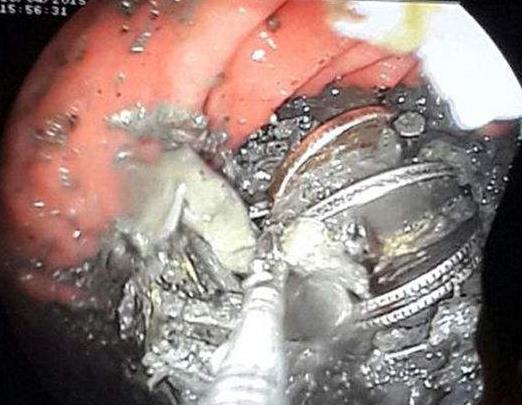

异食癖患者的胃

印度旁遮普邦巴廷达市的农民拉吉帕尔辛格因为胃痛到医院进行检查,医生在他的胃中发现了140多枚硬币、150多根钉子,以及大量的螺母、螺栓、磁铁、电池等异物。